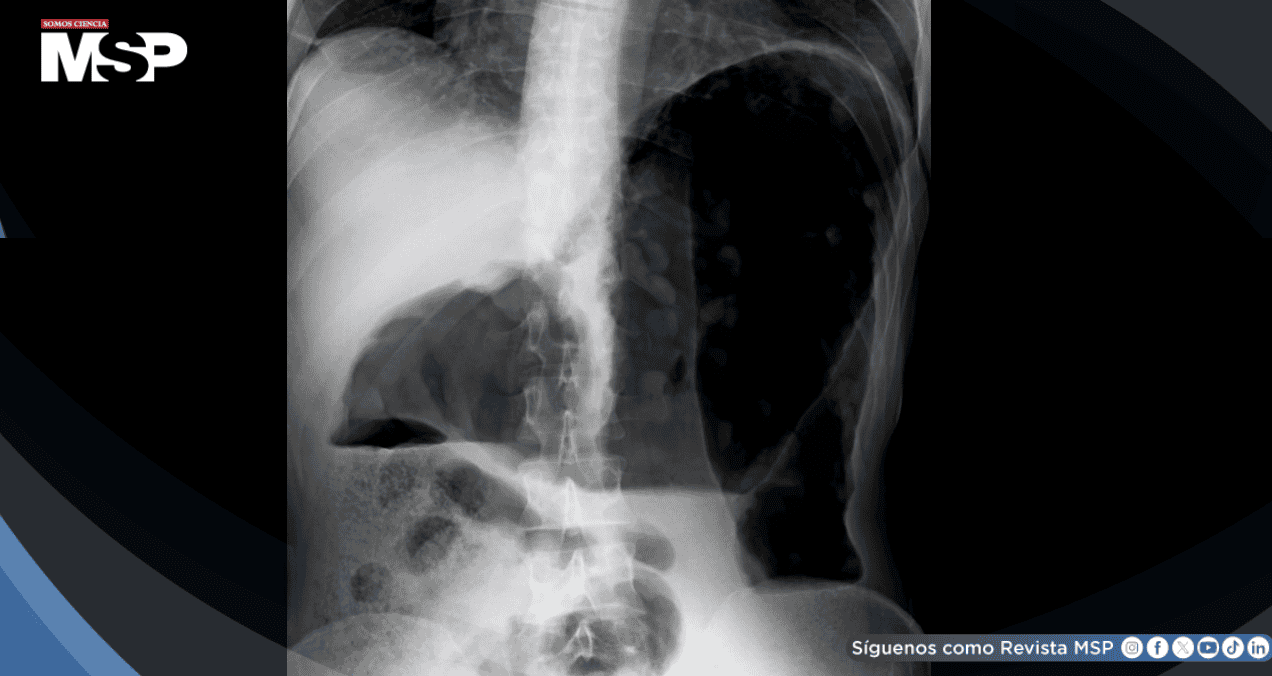

Una ecografía abdominal reveló la presencia de lesiones en el bazo, un órgano que hasta entonces había aparecido completamente normal en todos sus estudios previos. El paciente se encontraba asintomático, sin dolor, fiebre ni pérdida de peso, y su examen físico y análisis de sangre eran normales.

Ante la sospecha radiológica, se realizó una tomografía computarizada (TC) abdominal con contraste. Las imágenes mostraron varias lesiones quísticas en el bazo, la mayor de 24 milímetros, con un realce tenue del contraste.